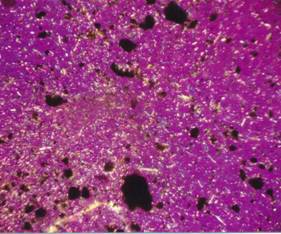

Galerie obrázků

Drobné jehličkovité krystaly močanu

sodného v polarizačním mikroskopu, zrnkový preparát,

zvětšeno 360x